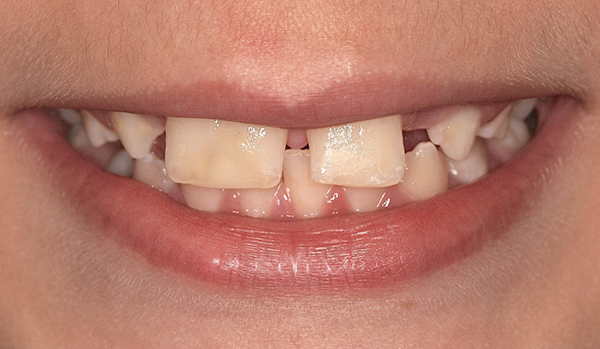

Fig 1 and Fig 2. Pretreatment photographs. Patient at 9 years of age on presentation.

A 9-year-old girl, referred to a prosthodontic office by her pediatric dentist, presented with her mother’s chief complaint: “The kids are teasing her about her big front tooth.” Findings from radiographic and clinical examinations revealed fused maxillary central-peg lateral incisors, teeth Nos. 7 and 8, and a congenitally missing lateral incisor, tooth No. 10 (Figure 1 through Figure 3). An implant was selected as the ideal treatment to replace tooth No. 10 when somatic growth was complete. A diagnostic wax-up was fabricated to determine if the fused tooth could be made to resemble two teeth, using pink composite to give the illusion of an interproximal papilla. The patient was referred for an orthodontic consultation to plan for closure of the diastema between teeth Nos. 8 and 9 and achievement of proper alignment for implant No. 10. The patient was also referred to a periodontist for pretreatment assessment of the tooth No. 10 site. An endodontist was consulted should exposure of the large pulp occur during tooth preparation.